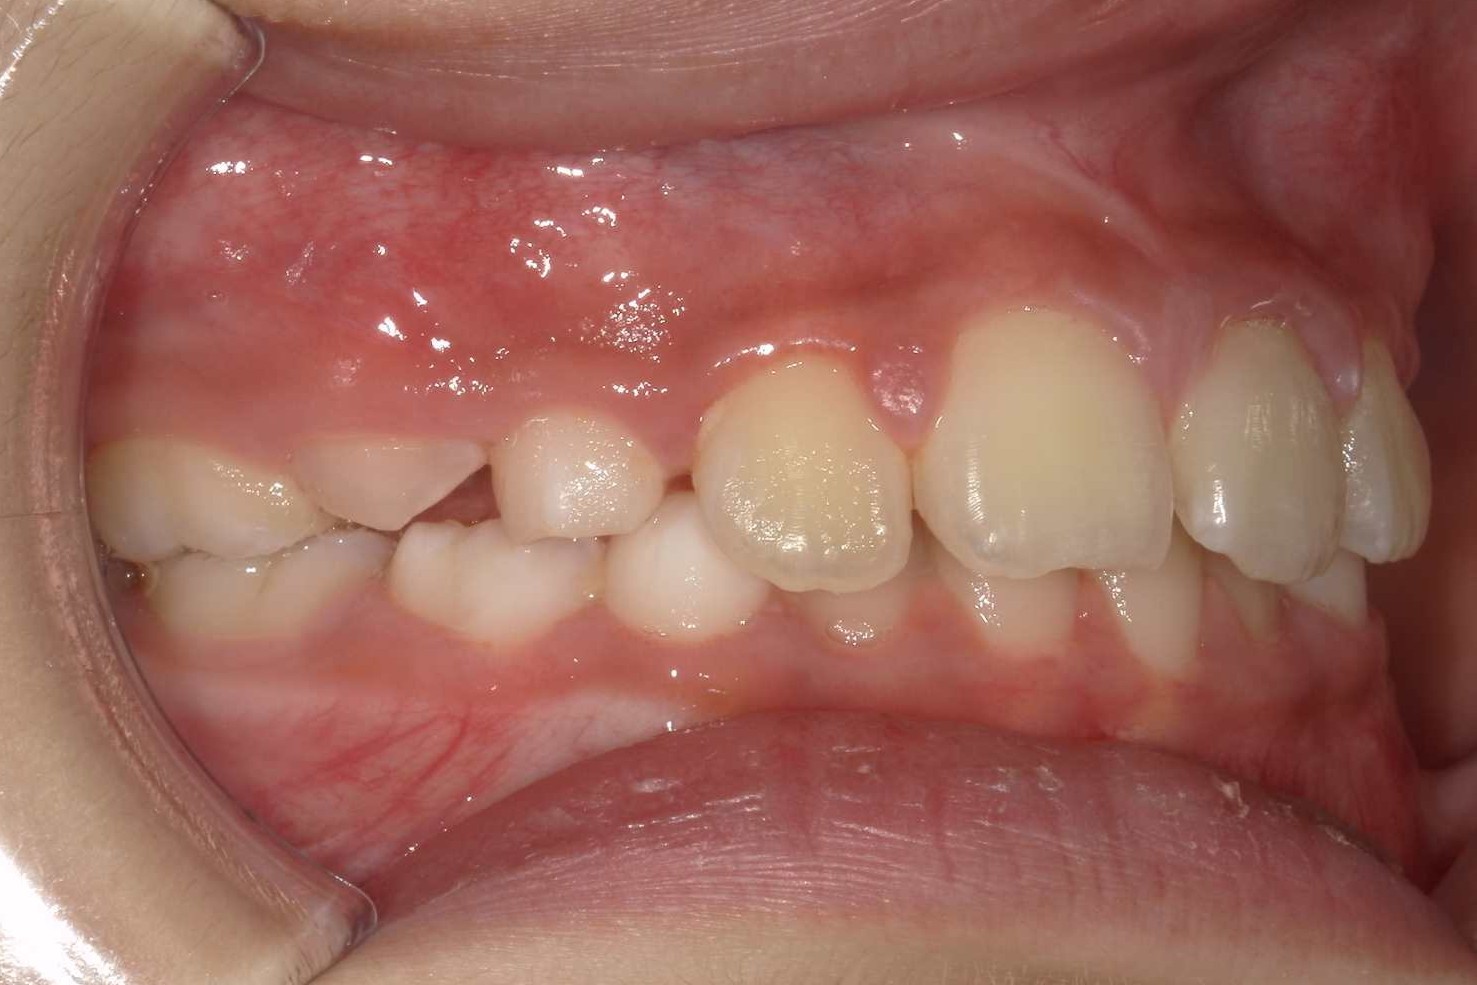

BEFORE

| 年齢 | 8歳 |

|---|---|

| 主訴 | 出っ歯、かみ合わせの深さを治したい |

| 症状 | 過蓋咬合を伴う上顎前突症例 |

| 治療内容 | 過蓋咬合を伴う上顎前突症例と診断し床矯正装置、セクショナルアーチ、機能的矯正装置を用いて治療を行いました。 |

| 抜歯部位 | 非抜歯 |

| 治療期間 | 3年半 |

| 費用(税込) | 825,000円(税込)別途処置料 |

| 治療のリスク | 虫歯、歯周病の悪化、歯肉退縮、歯根吸収、顎関節症の悪化、後戻り |